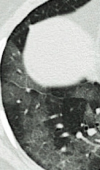

Case Report

CT Features of COVID-19: A Case Report

We describe here the Chest CT imaging features of a 68-year-old man presenting with fever (37.5 ℃), malaise, dyspnea and persistent dry cough for 7 ... Read more